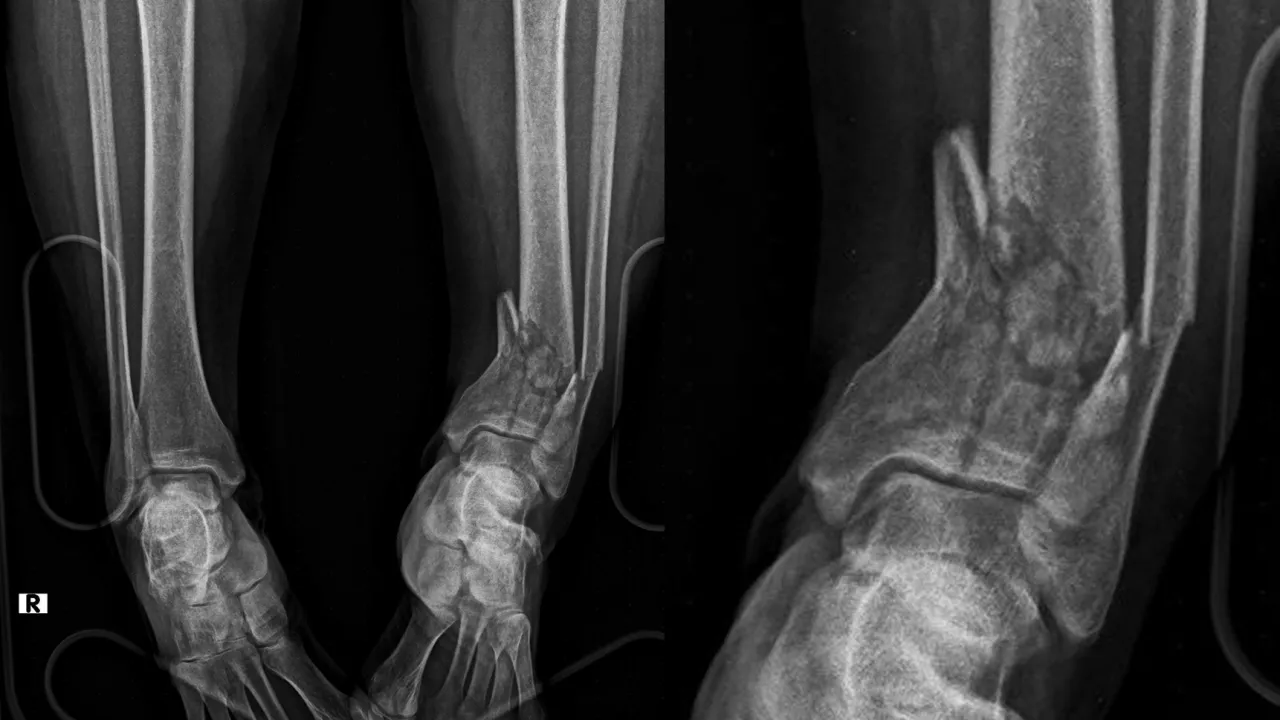

Travmalar, günlük yaşamda en sık karşılaşılan acil durumlardan biridir. Trafik kazaları, yüksekten düşmeler, spor yaralanmaları veya iş kazaları sonucu oluşan kırıklar, hızlı ve doğru müdahale edilmediğinde kalıcı sakatlıklara yol açabilir. Travma sonrası kırık cerrahisi, hastaların hayatını kurtaran ve fonksiyonel iyileşmelerini sağlayan en kritik tedavi alanlarından biridir. Kırık cerrahisini yapmayan ortopedist yoktur. Ancak burada yumuşak dokuya saygı gösterme ve bağların korunması, kırık tedavisi sonrasında kısa ve uzun vadede sonuçları etkileyen önemli faktördür.

▲ Plak ve Vida ile Tespit: Kemik parçaları anatomik pozisyona getirilip sabitlenir.

▲ Çivileme (İntramedüller Çivi): Uzun kemik kırıklarında güvenilir ve hızlı iyileşme sağlar.

▲ Eksternal Fiksatör: Özellikle açık kırıklarda veya çok parçalı kırıklarda geçici/kalıcı sabitleme yöntemi.

▲ Minimal İnvaziv Teknikler: Küçük kesilerle yapılan cerrahiler, daha az doku hasarı ve hızlı iyileşme sağlar.

Travma sonrası kırık cerrahisi, sadece bir kemik onarımı değil; hastanın yeniden ayağa kalkması, günlük hayatına dönmesi ve yaşam kalitesini geri kazanmasıdır. Modern görüntüleme teknikleri, güncel cerrahi yöntemler ve 7/24 acil müdahale sayesinde kırık tedavisinde yüksek başarı elde edilmektedir.